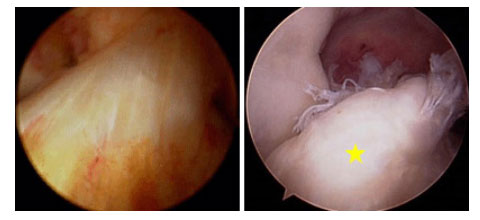

(Trái) Hình ảnh nội soi khớp của DCCT bình thường. (Phải) Hình ảnh nội soi khớp của DCCT bị đứt [vị trí sao vàng].